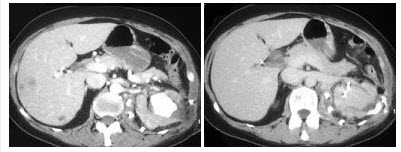

29、单项选择题

如图所示,这两个时相提示()

A.肾细胞癌

B.动静脉瘘

C.肾窦对比剂溢出

D.以上都有可能

E.以上都不是